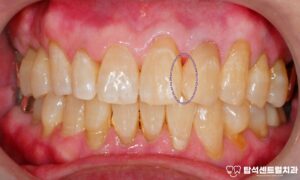

용현동 치과 외상으로 앞니 흔들림 있을 때, 치아를 보존하는 마지막 방법 : 잠간 고정술 설명 (+입술 봉합)

안녕하세요 용현동 치과 입니다. 빙판길 낙상, 구강 부상의 원인이 될 수 있습니다 겨울철에는 도로와 인도가단단하게 얼어붙는 경우가 많습니다.이런 빙판길에서 미끄러지면손을 짚기도 전에 얼굴부터바닥에 부딪히는 사고가 발생합니다. 특히 전치부는 충격에 취약한위치에…